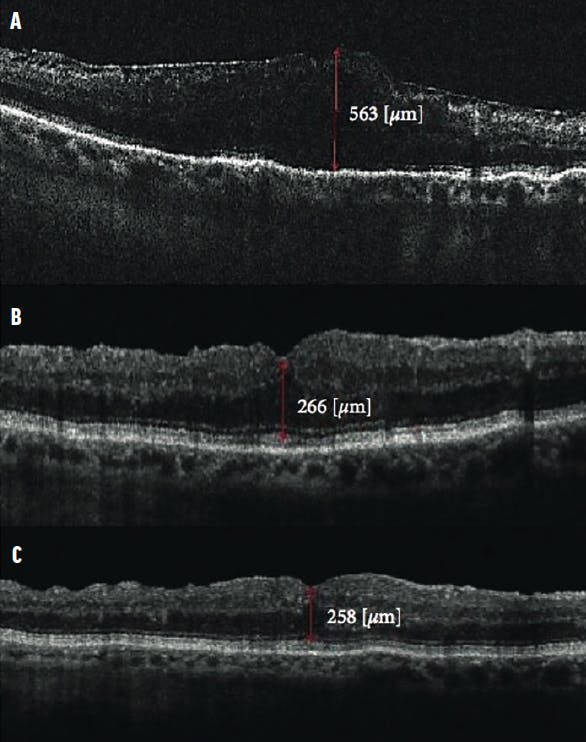

Intraoperative complications, especially peripheral retinal tears and the need for laser photocoagulation, were noted. The duration of surgery was recorded in five categories: 30 to 45 minutes, 46 to 60 minutes, 61 to 90 minutes, 91 to 120 minutes, and more than 120 minutes. Data gathered during follow-up visits at 1 week, 6 months, and final follow-up included BCVA, central macular thickness (CMT), and complications (Figures 1 and 2).

Figure 2. These OCT scans show a patient who underwent complete vitrectomy with ERM removal. The preoperative scan (A) shows the ERM with loss of foveal contour, CMT measuring 563 µm, and BCVA of 0.5 logMAR. The 1-month postoperative scan (B) shows a reduction in CMT to 266 µm and BCVA of 0.8 logMAR. At 1 year (C), CMT was 258 µm and BCVA had improved to 0.9 logMAR.